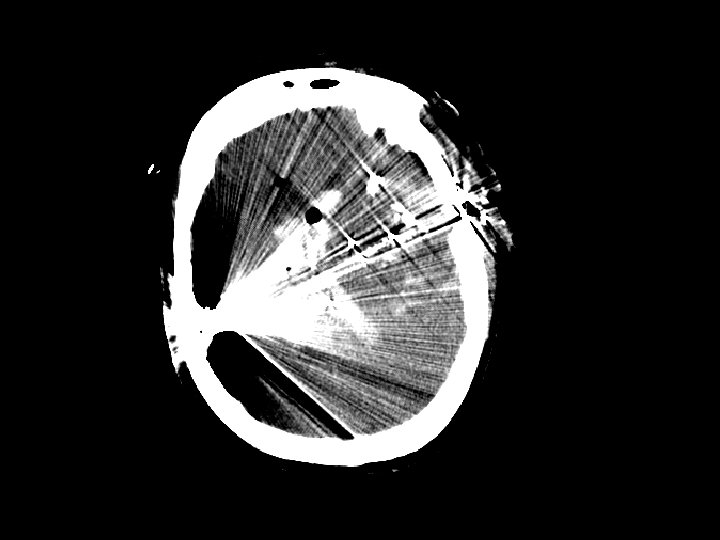

Penetrating Injury • Primarily gunshot wounds (GSWs) but also from stab wounds (SWs) • Higher rate in urban areas • Injuries that cross the midline have very poor outcomes • Periorbital/nasal region risk of infection